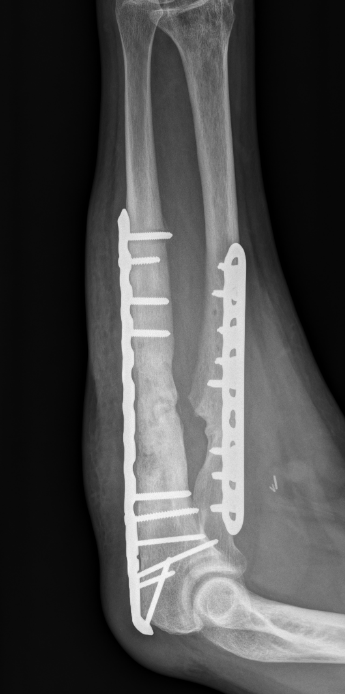

ORIF with plates

ORIF with DCP plates

Fixation with DCP plates